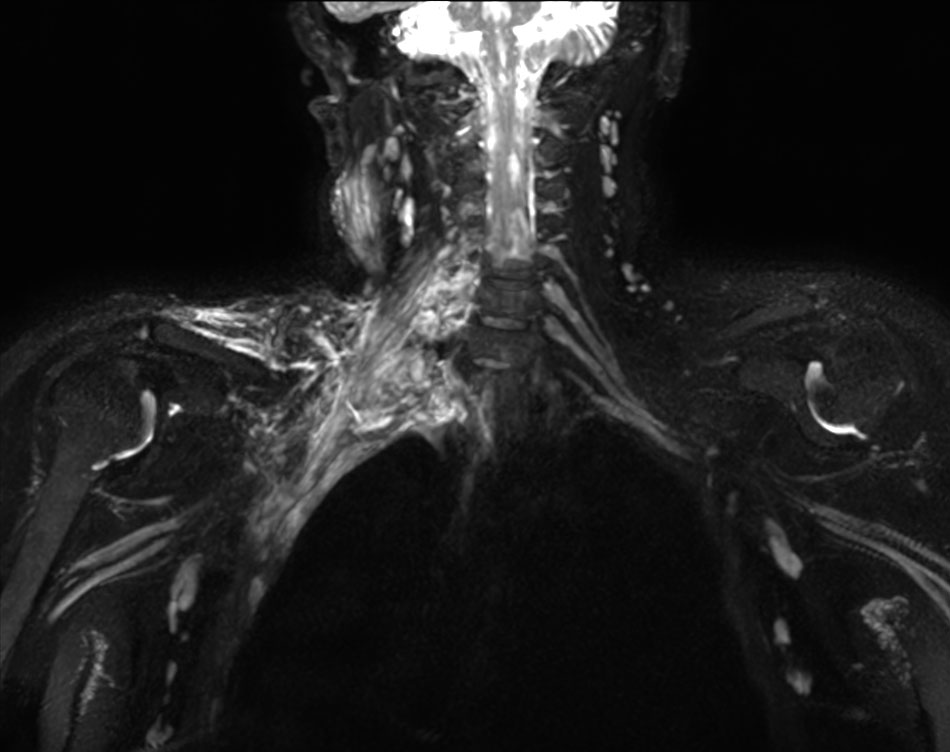

Coronal 3D NerveVIEW

Coronal 3D NerveVIEW (MIP)